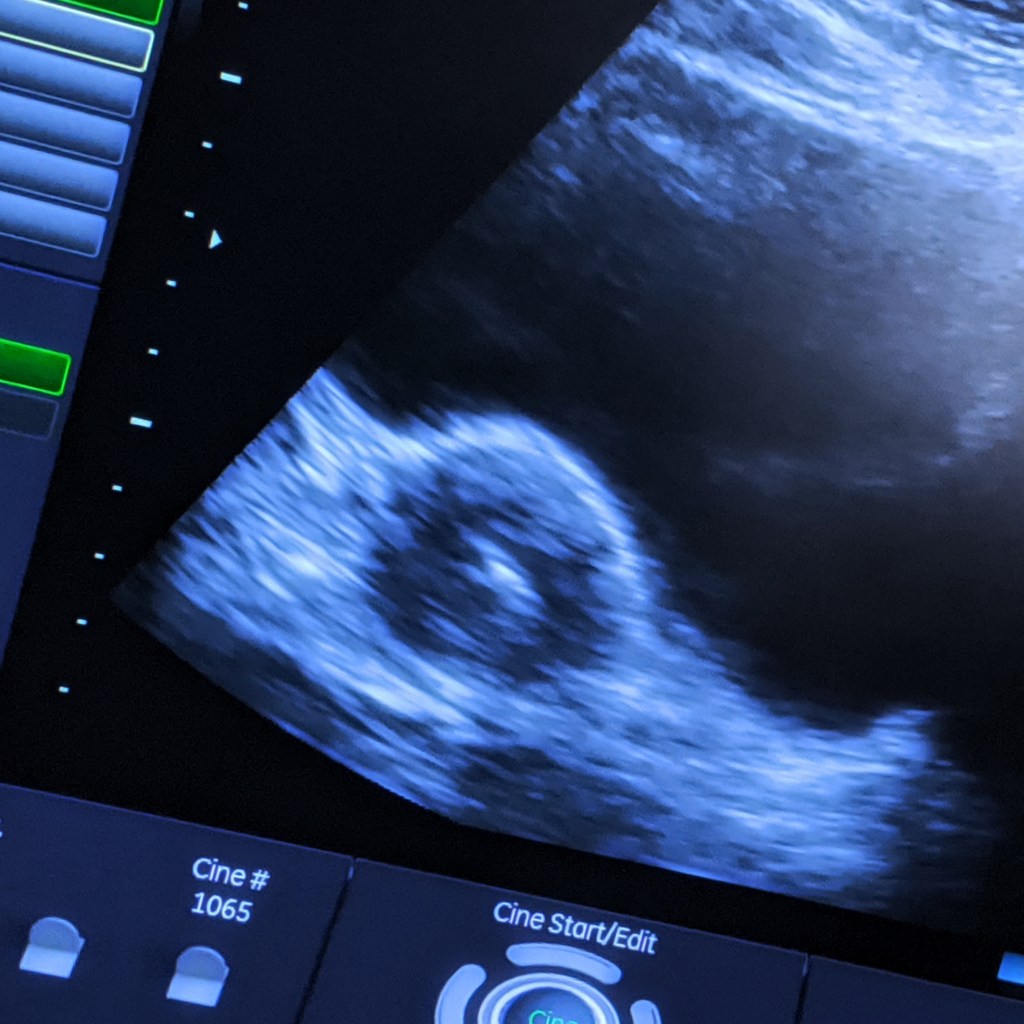

I had taken my phone with me as at my clinic they don’t give you a photo of your embry, or of your lining of where they’ve been put it back in, but some clinics do.

Anyway little embryo popped on the screen before it was whooshed inside me to sit in my womb and hopefully decide it’s nice and warm and wants to implant itself for the next 9 months.